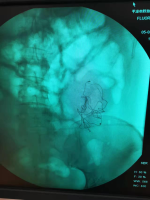

骑车遭绳割喉男孩家已申请低保 伤情危重引关注 关键词: 2026-04-14 09:48:38  光明网 河南沁阳一名13岁男孩骑车时被绳索割喉的事件持续受到关注。4月13日下午,男孩的母亲郝女士透露,由于伤势危重,孩子已于4月11日晚从河南当地医院转至北京儿童医院救治。目前孩子仍在ICU接受治疗,专家已进行会诊,但尚未给出具体医疗结论,手术方案也暂未确定。据此前报道,4月4日,郝女士的儿子在骑车前往补习班途中,颈部被一根突然出现的绳子缠住,随后被勒倒并割伤。经医院诊断,孩子气管、食管破裂,伤势十分危重,入院后即进入ICU抢救。这根绳子是村里一位村民为了阻止行人通过马路而拴上的,导致了这次惨剧的发生。柏香镇政府工作人员表示,郝女士通过相关平台的筹款工作已取得一定进展。官方慈善项目资金已对该家庭启动救助,当地还号召各村积极开展捐款活动,帮助孩子治疗。男孩家庭属于低保家庭,镇上和村里均已派人赶赴北京,协助郝女士夫妇处理孩子的治疗事宜。工作人员还提到,孩子出事当天,其家人已经报警。目前,公安机关仍在办理此案,事故调查结果尚未公布。 (责任编辑:zx0176)